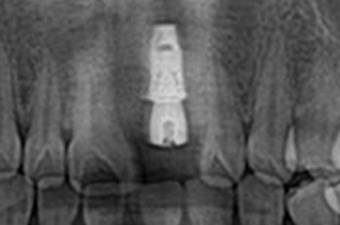

원데이 임플란트란?

심미적으로 중요한 앞니 또는 어금니에 파절이 생겨 발치를 해야하는 경우에

잇몸 질환이 없고 잇몸뼈가 튼튼한 경우에 한해 발치 당일에

임플란트 식립부터 임시치아까지 고난도 임플란트입니다.